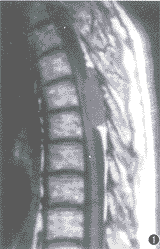

例1 男,65岁。下胸部束带感伴双下肢无力、行走不稳 4个月余。体检:T6以下浅感觉明显减退,双腹壁反射、提睾反射消失,双侧巴彬斯基征(+),双下肢肌力 IV级。脑脊液压力和常规检查正常。胸椎 X线片正常。 MRI扫描:T5~6水平椎管内脊髓后方硬膜外见一4.4 cm×1.5 cm大小的梭形病灶,基底靠后,最大处向两侧椎间孔方向生长。脊髓明显受压变细、前移。T1WI病灶与脊髓呈等信号(图1),T2WI上与脑脊液信号相似(图2)。注射钆喷替酸葡甲胺(Gd-DTPA)后,病灶呈明显均匀强化(图3)。MRI诊断:神经根瘤。手术所见:T5~6椎管内硬膜外见一肉红色梭形肿瘤,边界清楚,呈分叶状, 与硬脊膜有轻度粘连。未见明显增粗的供血动脉和引流静脉。邻近椎板和棘突骨质疏松,但无破坏。病理检查:肿瘤组织由大片壁薄、管腔扩大互相吻合、大小不一、外形不规则的血管间隙构成,壁为单层内皮细胞。血管间见散在的淋巴细胞和脂肪细胞(图4)。病理诊断:海绵状血管瘤。

图1~4 例1。 T1WI(图1)示 T5~6椎管内脊髓后方硬膜外梭形肿块与脊髓信号相等, 脊髓明显受压前移、变细,基底靠后。T2WI(图2)示病灶呈均匀高信号与脑脊液信号相似。注射钆喷替酸葡甲胺(Gd-DAPA)后(图3)病灶显著均匀强化。镜检(图4):肿瘤主要由扩张而大小不等的血管间隙构成,壁薄,由单层内皮细胞构成(HE 20×10)